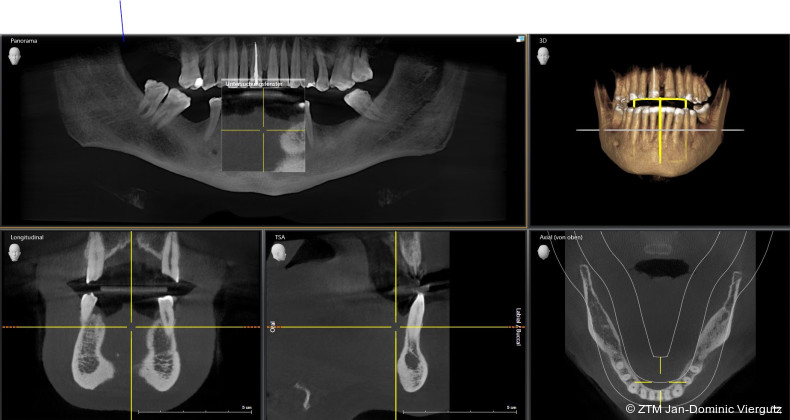

Nach der erfolgreichen Eingliederung der Michigan-Schiene (Erkodur, Erkodent) und dem deutlichen Rückgang der Kiefergelenkschmerzen wurde die Behandlung gemäß dem Therapieplan fortgesetzt. Zunächst erfolgte die erneute Wurzelbehandlung am Zahn 11, gefolgt von der schablonengeführten Implantation (DTX Studio Clinic, Nobel Biocare) von drei Implantaten (NobelReplace, Nobel Biocare) im Unterkiefer (36, 37 und 46). Alle chirurgischen Maßnahmen wurden in Dämmerschlaf-Narkose unter Begleitung eines Anästhesisten durchgeführt.

Nach einer Einheilzeit von fünf Monaten zeigten sich stabile Verhältnisse: Die Kiefergelenkschmerzen waren weiterhin nicht vorhanden, die Implantate wiesen eine sichere Osseointegration auf und Zahn 11 blieb beschwerdefrei. Daraufhin konnte die Präparation der Zähne unter erneuter Narkose erfolgen. Die digitale Abformung wurde mit dem iTero-Intraoralscanner (Align Technology) vorgenommen und ermöglichte eine präzise Erfassung der klinischen Situation. Direkt im Anschluss wurde das Provisorium mittels tiefgezogenen Formteils (Erkodur, Erkodent) erstellt und eingesetzt.